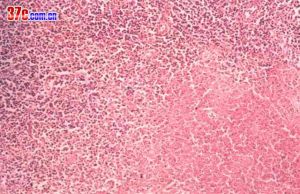

1、類腫瘤型 病變多起於鼻部,亦有首發於上齶、咽部,然後累及鼻部。病變主要位於面中線部位及上呼吸道,以進行性肉芽性潰瘍壞死為主,其破壞性甚為廣泛,可侵及骨和軟骨,以致毀容。晚期病人多死於大出血或衰竭,屍檢材料中無動脈周圍炎現象。本病病理變化差異性較大,主要見於以下4種類型:

(1)非特異性炎性肉芽組織含多種形態的炎性細胞;

(2)非特異性炎性肉芽組織含有大量組織細胞;

(3)非特異性炎性肉芽組織有明顯壞死;

(4)非特異性炎性肉芽組織含許多巨細胞。上述4種類型,多呈混合存在,且常以淋巴細胞為主,混有相當多的漿細胞和數量不一的組織細胞。這些細胞有明顯的以血管為中心,圍繞血管而浸潤的傾向。雖然這些細胞中有中等度的異型性,但仍不能診斷為惡性腫瘤。Wegener肉芽腫的病理變化雖然也是非特異性肉芽腫,但其特徵是有多核巨細胞和壞死性血管炎,這是惡性肉芽腫與Wegener肉芽腫的病理變化雖然也是非特異性肉芽腫,但其特徵是有多核巨細胞和壞死性血管炎,這是惡性肉芽腫與Wegener肉芽腫的鑑別診斷標準。